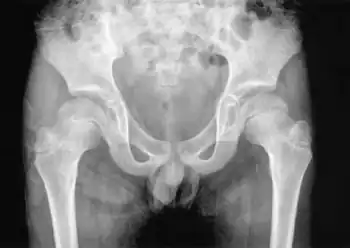

Coxa vara is a deformity of the hip, whereby the angle between the head and the shaft of the femur is reduced to less than 120 degrees. This results in the leg being shortened and the development of a limp. It may be congenital and is commonly caused by injury, such as a fracture. It can also occur when the bone tissue in the neck of the femur is softer than normal, causing it to bend under the weight of the body. This may either be congenital or the result of a bone disorder. The most common cause of coxa vara is either congenital or developmental. Other common causes include metabolic bone diseases (e.g. Paget's disease of bone), post-Perthes deformity, osteomyelitis, and post traumatic (due to improper healing of a fracture between the greater and lesser trochanter). Shepherd's Crook deformity is a severe form of coxa vara where the proximal femur is severely deformed with a reduction in the neck shaft angle beyond 90 degrees. It is most commonly a sequela of osteogenesis imperfecta, Pagets disease, osteomyelitis, tumour and tumour-like conditions (e.g. fibrous dysplasia).

In early skeletal development, a common physis serves the greater trochanter and the capital femoral epiphysis. This physis divides as growth continues in a balance that favors the capital epiphysis and creates a normal neck shaft angle (angle between the femoral shaft and the neck). The corresponding angle at maturity is 135 ± 7 degrees. Another angle used for the measurement of coxa vara is the cervicofemoral angle which is approximately 35 degrees at infancy and increases to 45 degrees after maturity.

X-ray: decreased neck shaft angle, increased cervicofemoral angle, vertical physis, shortened femoral neck decrease in femoral anteversion. HE angle (Hilgenriener epiphyseal angle- angle subtended between a horizontal line connecting the triradiate cartilage and the epiphysis); normal angle is <30 degrees.